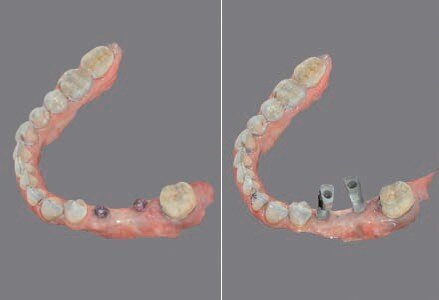

Fig. 6 - Progettazione dima chirurgica.

Dopo aver valutato con la paziente tutti i pro e i contro abbiamo deciso di prediligere la scelta dei REX PiezoImplant. È stata eseguita un’impronta digitale che è stata accoppiata tramite il software di progettazione all’esame radiografico tridimensionale. Sono stati scelti due impianti REX PiezoImplant 1,8 x 11. L’impronta digitale della situazione pre-intervento della paziente ci ha permesso di utilizzare quest’ultima (come ceratura diagnostica) per programmare il posizionamento implantare in modo protesicamente guidato. La pianificazione software della fase chirurgica e l’utilizzo di una guida per il corretto posizionamento dell’impianto “asse implanto- protesico”, ci hanno permesso non solo di ottenere il posizionamento implantare nel rispetto dello spessore osseo disponibile “asse anatomico” ma anche di ricercare la migliore soluzione protesica avvitata, “asse protesico”, per una sensibile riduzione del rischio di errore. È stata creata una dima chirurgica che ci ha permesso di riportare nel cavo orale la programmazione dell’inserimento implantare che avevamo pianificato virtualmente. La metodica Rex permette di utilizzare una slitta che prevede una chirurgia guidata con sistema Pilot utilizzando l’inserto W2. Sono state raccordate le due preparazioni e le abbiamo estese con l’inserto OT7S3 che ci ha permesso di ottenere una maggiore elasticità ossea.

Dopo 6 mesi abbiamo effettuato delle Rx di controllo e misurato nuovamente il valore ISQ. Dopo aver riscontrato valori positivi abbiamo svitato le viti di guarigione e abbiamo avvitato gli specifici REXmarkers direttamente sugli impianti REX PiezoImplant. Abbiamo quindi effettuato un’impronta digitale con l’ausilio di uno scanner digitale Carestream 3600. Con l’esportazione dei file STL è stato possibile realizzare una protesi avvitata disegnata con Exocad*** che dispone al suo interno delle librerie protesiche REX PiezoImplant. È stato quindi consegnato il manufatto protesico definitivo che è stato avvitato a 25 N dopo aver controllato radiograficamente il corretto accoppiamento.